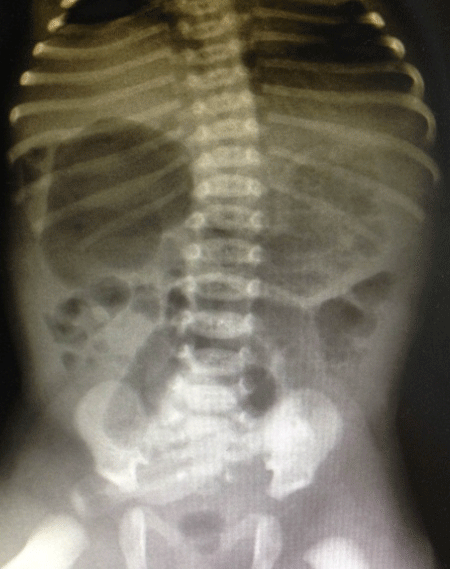

On day of life three, the patient underwent a diagnostic laparoscopy. Intra-operative findings included a 43 cm cystic mass in the right upper quadrant consistent with a duplication cyst (Fig. 4), as well as a freely mobile cecum in the left abdomen consistent with malrotation. A directed laparotomy (guided by the initial laparoscopic evaluation) with resection of duplication cyst and anastomosis of the small bowel along with a Ladd’s procedure were performed. No classical Ladd’s bands could be identified although there were numerous abnormal mesenteric bands compressing the distal small bowel that were divided. The patient was discharged home uneventfully after a two-week stay in the neonatal intensive care unit.

Figure 4: Operative findings of jejunal duplication cyst |